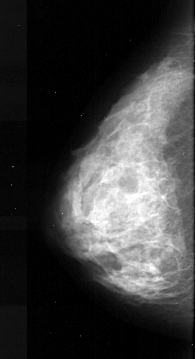

A_1041_1.LEFT_MLO

LEFT_CC LINES 4306 PIXELS_PER_LINE 2341 BITS_PER_PIXEL 16 RESOLUTION 42 NON_OVERLAY

LEFT_MLO LINES 5506 PIXELS_PER_LINE 2386 BITS_PER_PIXEL 16 RESOLUTION 42 NON_OVERLAY